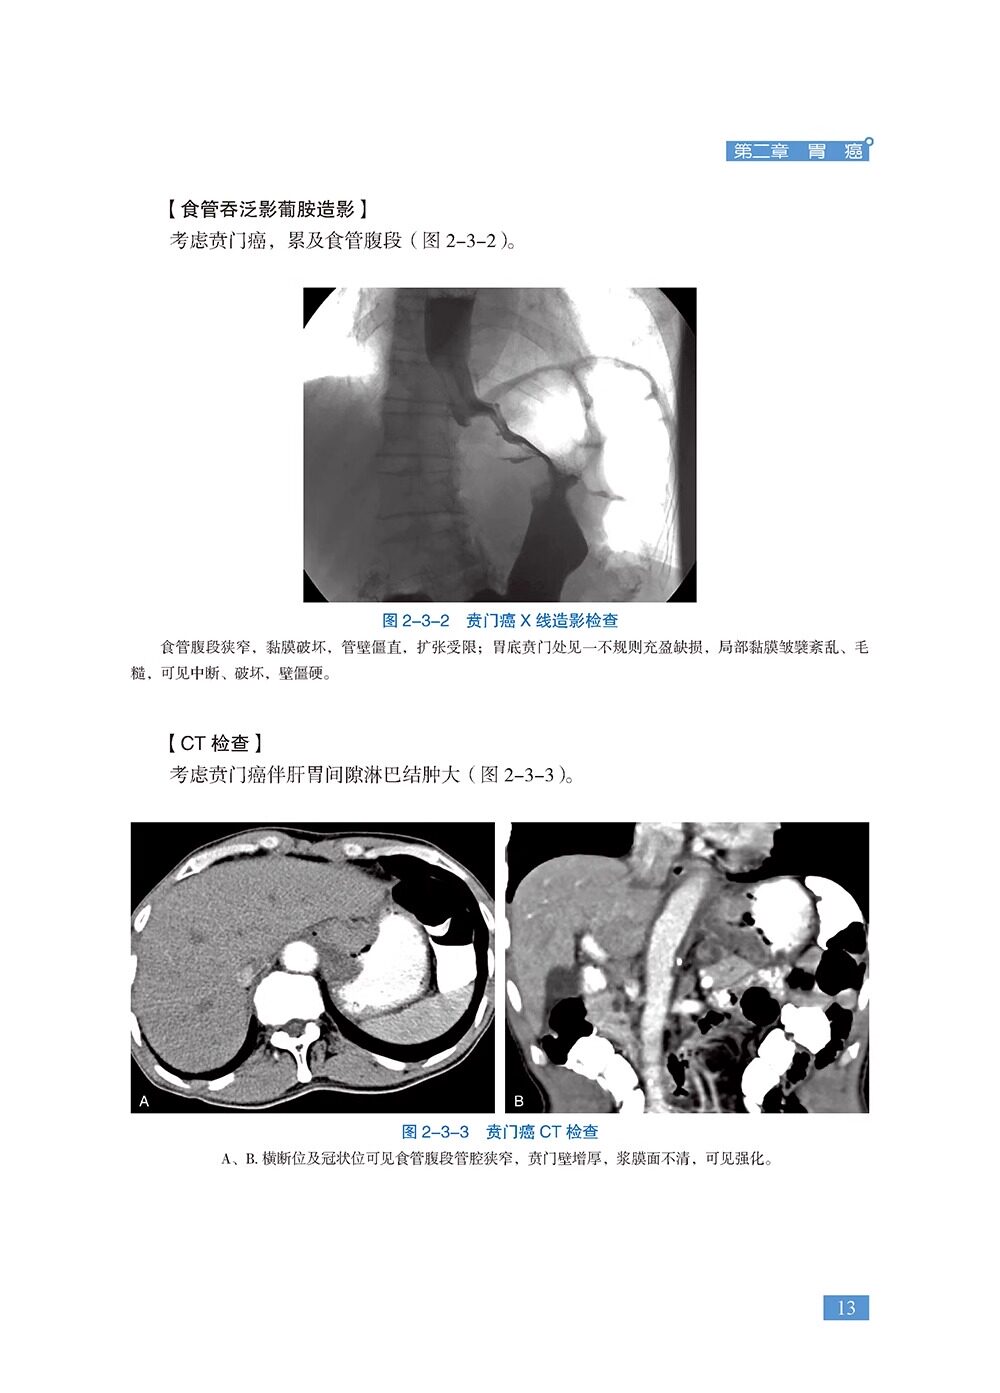

本书是《胃肠疾病超声诊断学》的姊妹篇,共18章,精心挑选了120个胃肠超声经典病例、疑难病例、罕见病例及误诊病例。涵盖各种胃肠道肿瘤、消化性溃疡、炎症性肠病、急腹症、先天异常、胃肠周围血管疾病等内容。每个病例从病史、体格检查、实验室检查、超声检查、其他影像检查、诊疗经过、病理诊断等方面进行详细阐述,并针对病例的超声特征及误诊原因等进行精准解析。全书精选了700余幅超声、CT、MRI、病理等图片,内容丰富、图文并茂,具有很强的实用性和指导性。适合各级超声医师及相关学科临床医师、医学院校师生阅读。